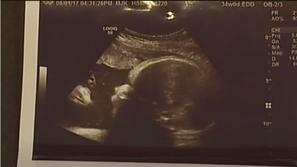

Ultrazvok Starša šokirana, ko sta dobila slike dojenčice po ultrazvoku To je jasen znak, trdita starša.

Magazin Angel na ultrazvoku? Britanka Jennifer Holman je prepričana, da je na ultrazvočnem posnetku angel.